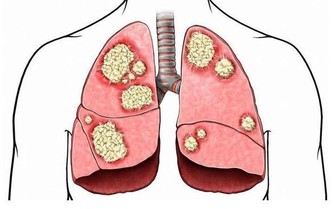

蘿蔔有破氣作用,會大大減弱中藥滋補功效。(以上皆為網路圖片) 9、滋補類中藥+蘿蔔 滋補類中藥通過補氣,進而滋補全身氣血陰陽,而蘿蔔有破氣作用,會大大減弱滋補功效,因此服用滋補類中藥期間忌食蘿蔔。 10、抗過敏葯+起士、肉製品 服用抗過敏藥物期間忌食起士、肉製品等富含組氨酸的食物。因為組氨酸在人體內會轉化為組織胺,而抗過敏葯抑制組織胺分解,因此造成人體內組織胺蓄積,誘發頭暈、頭痛、心慌等不適癥狀。